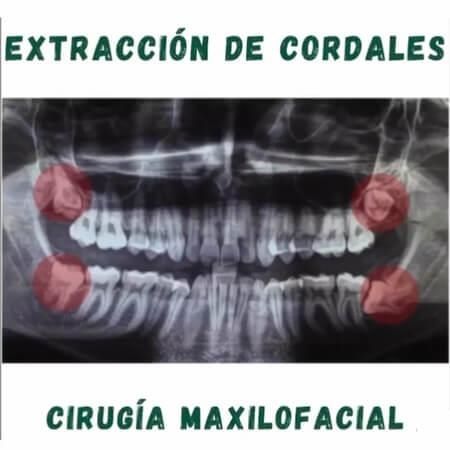

Procedimientos y tratamientos:

Recomendado 100% me realice la cirugía de cordales, cero dolor Una excelente atención, poca inflamación y rápida recuperación.

Excelente cirujano 100% se los recomiendo pues me saque dos cordales y no hubo dolor en el procedimiento y una rápida recuperación ??

Tiene buena mano el Dr. La extracción de cordales fue sin dolor. Buena recuperación.